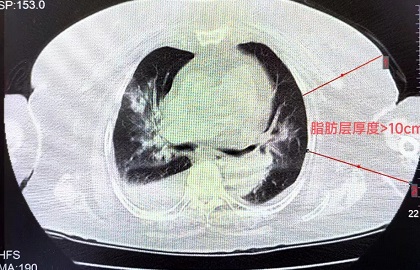

- 福建女子睡一觉“断气”400多次,差点要了命!病因很多人都有